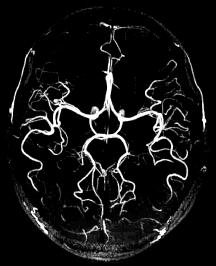

Here are 3 angiograms. Each case represents either a thrombotic, hypoperfusion, and hemorrhagic stroke. Which is which?

In the absence of hemorrhage or thromboembolic event, would you expect to see any abnormality on the angiogram (assuming the patient recovered)?